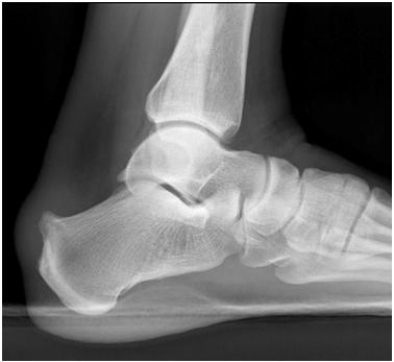

22

What can you tell about this patient whose lateral calcaneus radiograph is shown?A) The patient is a long-distance runner with chronic heel pain.

B) The patient has lost the ability to plantar flex at the ankle.

C) The patient has cancer with new onset of foot pain.

D) This patient landed on his feet from a 12-foot fall and also has back pain.